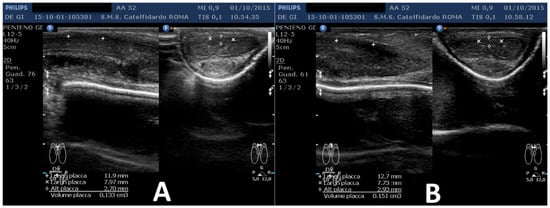

| 1 | 31 years | Chronic prostatitis and associated anxious and depressive state. | Distal third | (A) 15.1 × 12.1 × 3.7 mm volume = 353 mm3 (B) No plaque detected | (A) 10-degree ventral curvature + 15-degree left curvature (B) None | VAS score = 8 Pain disappeared after 12 months | 26 > 27 | 30 months | Orally: propolis 600 mg + bilberry 160 mg + silymarin 400 mg + ginkgo biloba 250 mg + L-carnitine 1000 mg + coenzyme Q10 100 mg + Boswellia 200 mg + Vitamin E 30 mg/daily/for 30 months + topically: diclofenac gel 4%/2× daily for 30 months Note: The patient refused periplaque penile injections with pentoxifylline |